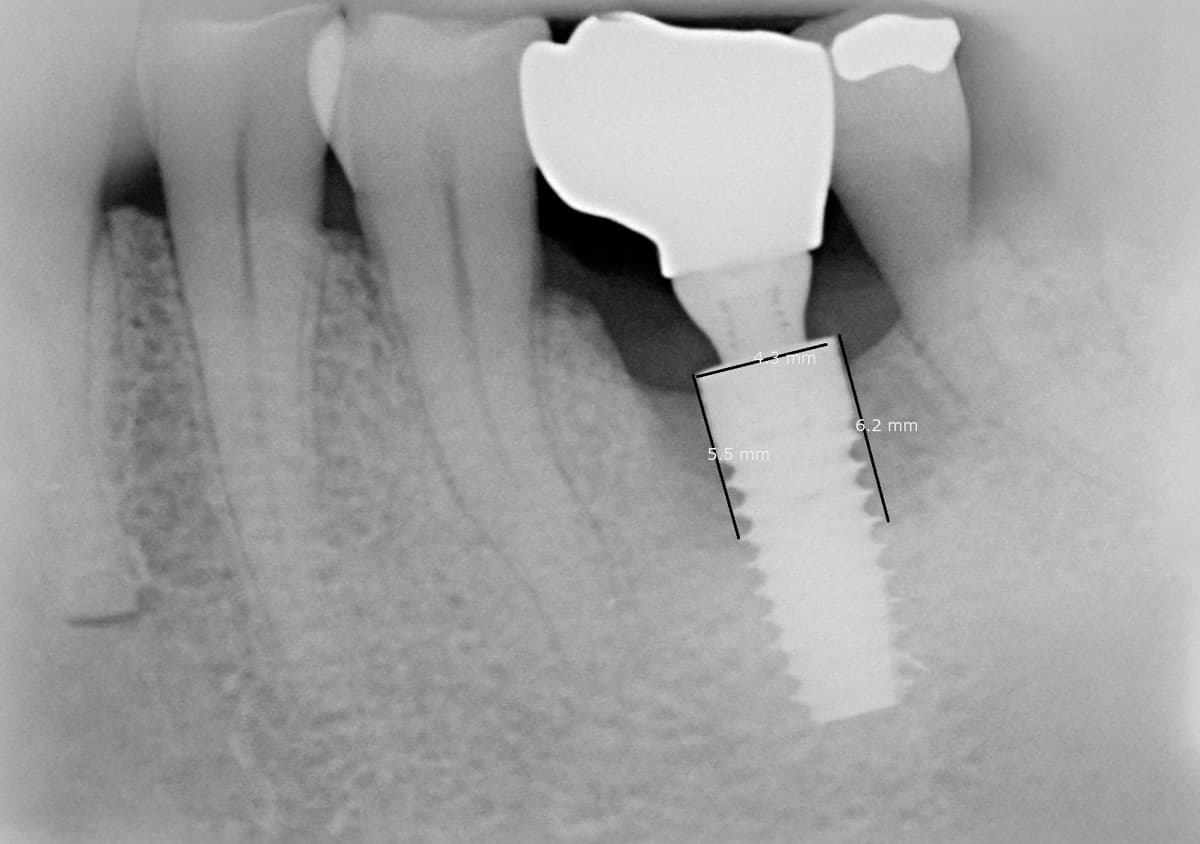

La perimplantite è una patologia infiammatoria che colpisce i tessuti intorno agli impianti dentali, causando il riassorbimento dell'osso di supporto e, nei casi più gravi, la perdita dell'impianto stesso. Le cause possono essere molteplici e vanno da placca batterica e tartaro causate dalla scarsa igiene orale, dal fumo e alle malattie sistemiche.

Il trattamento della perimplantite prevede una pulizia profonda delle superfici implantari, l'uso di laser o farmaci antibatterici e, nei casi avanzati, procedure di rigenerazione ossea per ristabilire il supporto dell'impianto.